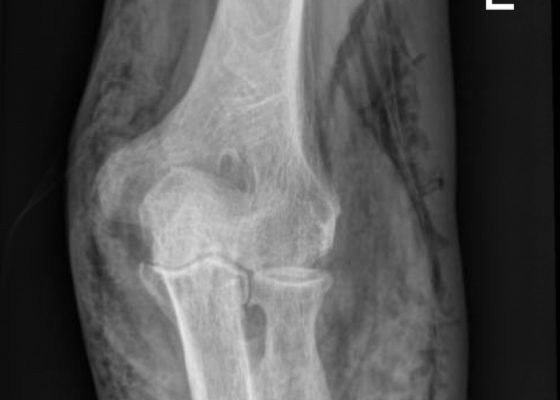

Subcutaneous Emphysema in Non-Necrotizing Soft Tissue Injury

DOI: https://doi.org/10.21980/J8432MX-Rays of the elbow revealed diffuse striated lucencies throughout the soft tissue, consistent with extensive subcutaneous air throughout the superficial and deep tissues. There was no evidence of a fracture.